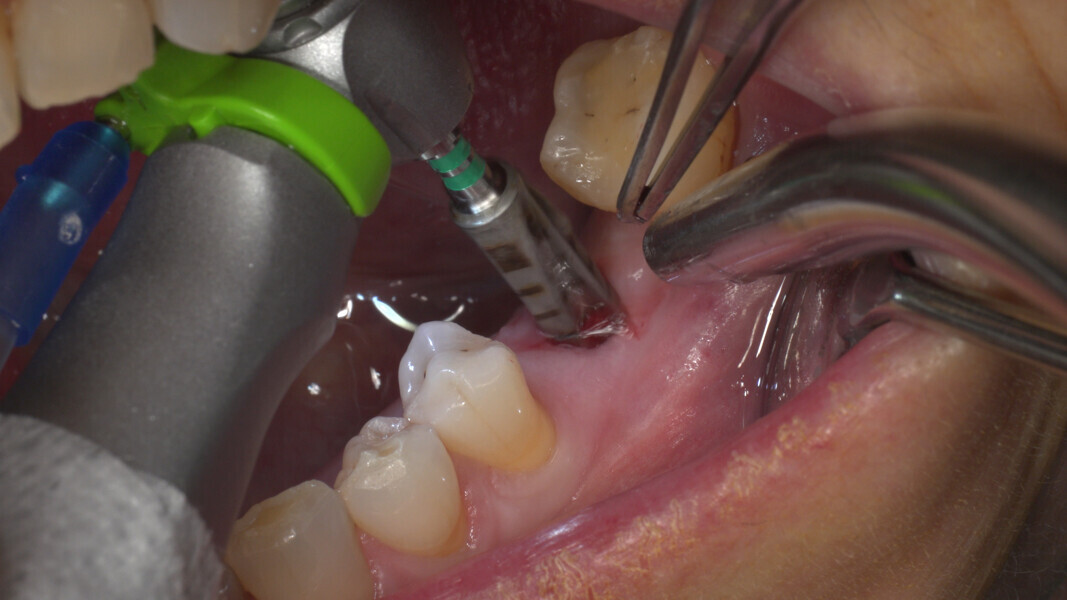

Conventional and immediate loading with final n!ce screw-retained crowns